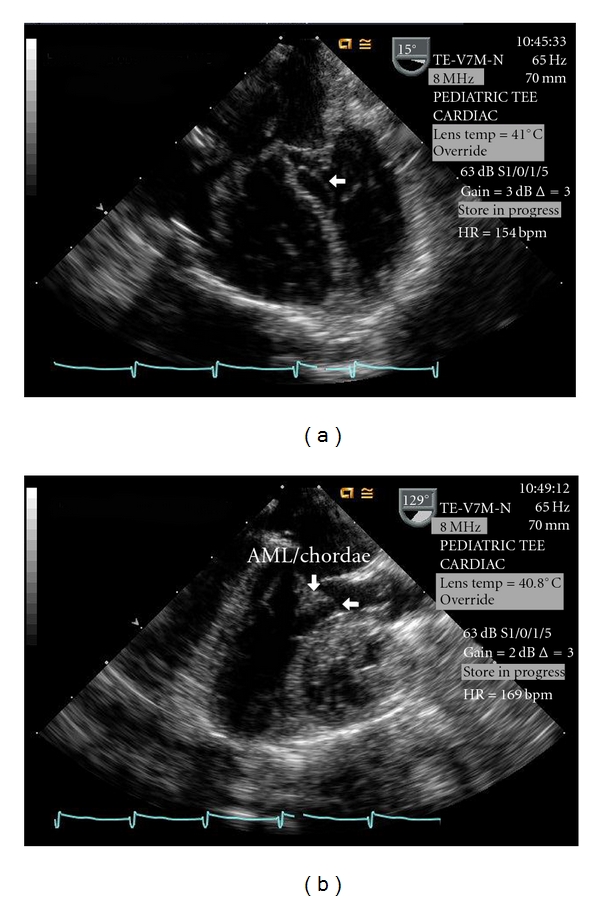

Dissecting ventricular septal hematoma (DVSH) rarely occurs after repair of a ventricular septal defect (VSD) but can lead to serious complications such as septal rupture, myocardial rupture, cardiogenic shock, heart block, outflow obstruction, cardiac tamponade, abscess transformation, and death. This paper describes the diagnosis and management of acute, severe, left ventricular outflow tract obstruction caused by the development of a DVSH after VSD repair.